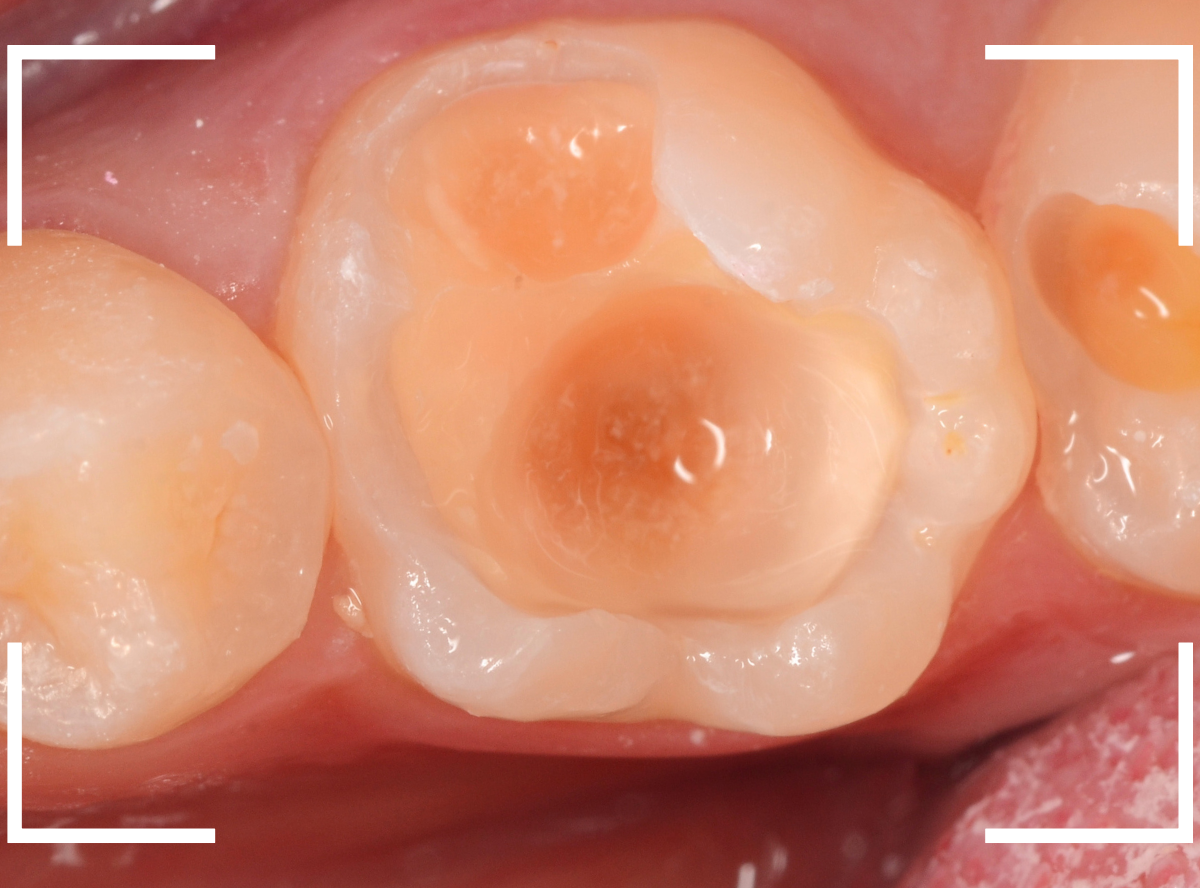

今回は、歯の溝(小窩裂溝)の下が深い虫歯になっていた方のケースです。

小窩裂溝とは、歯の表面にある小さな窪みや穴、溝のことです。

小窩裂溝は虫歯になりやすい上、歯の内部で広がっていることが多いのが特徴です。

この方は、以前にセメントで小窩裂溝を埋めて虫歯予防処置を施した形跡がありますが、それでも虫歯になってしまいました。

レントゲン写真で確認します。

青い線が神経、赤い線が虫歯の部分です。

やはり、小窩裂溝の中で大きな虫歯になっています。